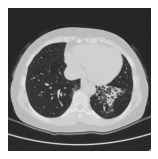

Paciente feminina de 22 anos procura

atendimento por hemoptise eventual, tosse

produtiva e pneumonias frequentes (em

média 3 por ano). Durante avaliação, foi

solicitada tomografia de tórax. Referente às

alterações presentes na seguinte imagem,

assinale a alternativa correta.